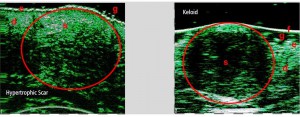

-Διαφοροποίηση μεταξύ υπερτροφικών και χηλοειδών ουλών